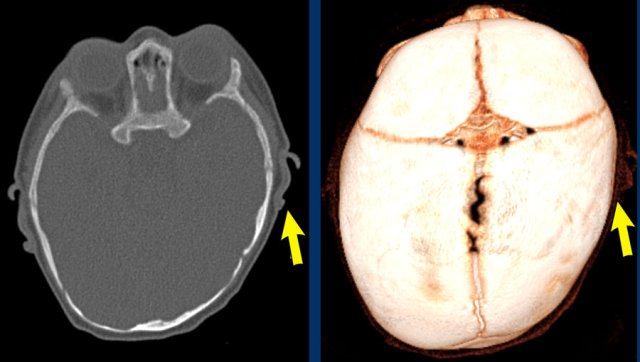

3D CT

The images show open sutures in a child with a physiologically closed metopic suture (arrow).

Images courtesy of Dr K.A. Eley and Dr C. Delso Images courtesy of Dr K.A. Eley and Dr C. Delso